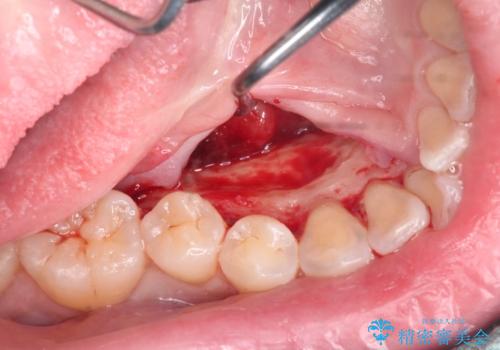

上下の歯のがたつきを改善するマウスピース矯正治療と、下顎に見られる大きな骨隆起を外科的に除去する治療計画を進めていきます。

骨隆起の除去は、静脈内鎮静法を用いてほとんど記憶のないうちに行うことができます。

歯並びが改善したとともに、骨隆起を除去したことで舌をしまうスペースも増え安定した口腔内環境を確立することができました。

外科処置の注意事項(リスク・副作用など)

- 外科手術のため、術後に出血、痛みや腫れ、違和感を伴います